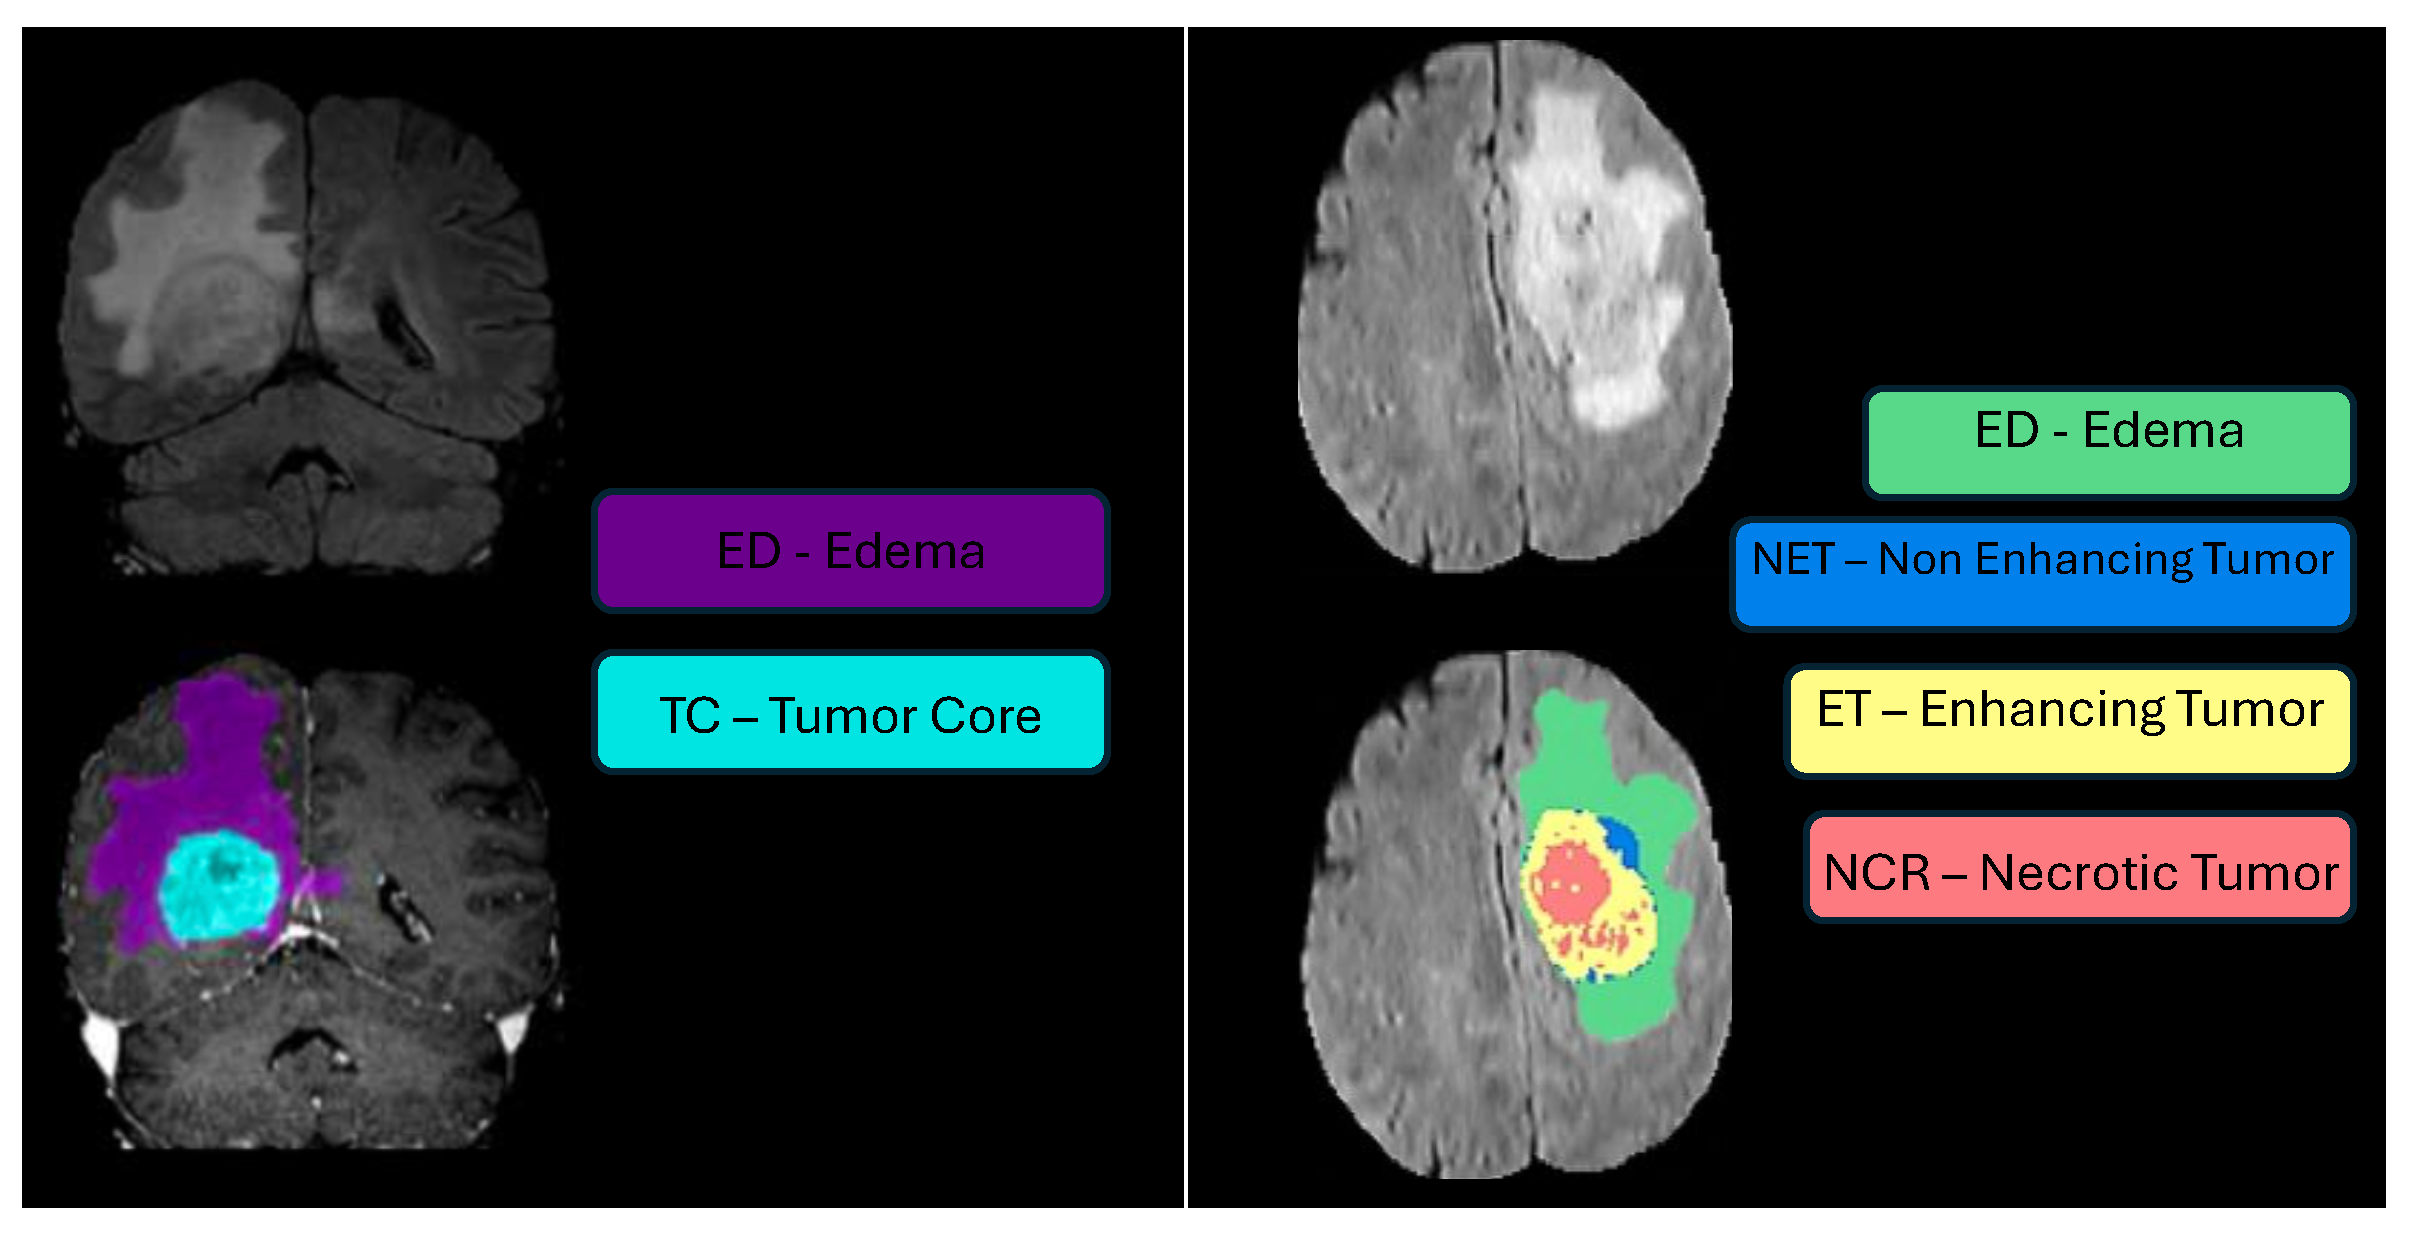

- Number of classes: three class labels:

- Label 1—NCR/NET: necrotic and non-enhancing tumor;

- Label 2—ED: the peritumoral edema;

- Label 4—ET: the GD-enhancing tumor;

- Label 0: everything else.

- Challenge Data: Task 1 involved developing methodologies for segmenting gliomas on pre-operative scans, utilizing clinically-acquired training data. The analyzed sub-regions included: (1) the enhancing tumor (ET), (2) the tumor core (TC), and (3) the whole tumor (WT). Specifically, WT is defined as the combination of labels 1, 2, and 4; TC comprises labels 1 and 4; and ET corresponds solely to label 4. Figure 5 illustrates how the previous four-class labeling (top panel) was refined in 2017 by omitting the non-enhancing tumor label (NET) and merging it with the necrotic core (NCR). This shift simplified annotations and ensured greater consistency in segmentation tasks across diverse data sources.

- Label 1—NCR: necrotic tumor;

- Label 2—ED: peritumoral edema;

- Label 4—ET: GD-enhancing tumor;

- Number of classes for tasks 1–8: three class labels:

- Label 1—NCR: necrotic tumor core;

- Label 2—ED: peritumoral edematous/invaded tissue;

- Label 3—ET: GD-enhancing tumor;

- Segmentation—BraTS-Africa Dataset: All imaging data were reviewed and manually annotated by board-certified radiologists specializing in neuro-oncology, following the BraTS pre-processing and annotation protocols. Figure 9 demonstrates the new segmentation labeling introduced in 2023, which is also employed in the BraTS-Meningioma and BraTS-Metastasis 2023 challenge. This labeling system delineates three tumor sub-regions:

- (a)

- Enhancing tumor (ET): represents all tumor portions with a noticeable increase in T1 signal on post-contrast images compared to pre-contrast images, excluding adjacent blood vessels, intrinsic T1 hyperintensity, or abnormal signal in non-tumor tissues.

- (b)

- Non-enhancing tumor core (NETC): includes all non-enhancing tumor core areas, such as necrosis, cystic changes, calcification, and other non-enhancing components. Intrinsic T1 hyperintensity (e.g., intratumoral hemorrhage or fat) is also included.

- (c)

- Surrounding non-enhancing FLAIR hyperintensity (SNFH): covers the full extent of FLAIR signal abnormalities surrounding the tumor that are unrelated to the tumor core. For meningiomas, this corresponds to “vasogenic edema”, excluding non-tumor-related FLAIR abnormalities like prior infarcts or microvascular ischemic changes [10].